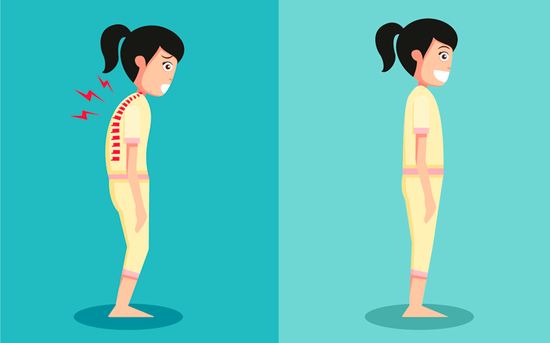

改善不良姿势

姿势不良与脊柱侧弯可互为因果,并恶性循环。因此控制脊柱侧弯的发展需重视不良姿势的纠正。抬头挺胸,勿弯腰驼背,尽量避免长时间翘二郎腿的姿势。

千万别做低头族

现代人玩平板电脑、手机、当低头族,长时间维持不良姿势,是一种常见的现象,也是造成脊柱侧弯的一个不可忽视的原因。

不良的姿势会导致脊椎两侧旁边的肌肉和筋膜因为两边不平衡而拉扯,肌肉容易疲劳僵硬。久而久之的姿势不良,就会造成慢性的肌筋膜发炎,脊椎也会较容易退化,造成脊柱侧弯的后果。

不想脊椎变形,

就从改变坐姿和站姿开始!